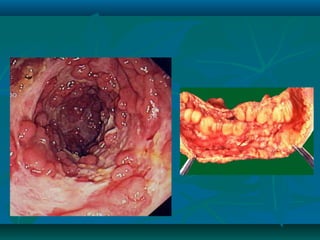

Colonic pseudopolyps

serpiginous ulcer, a classic finding in Crohn's disease

Endoscopic image of Crohn's colitis showing deep ulceration.